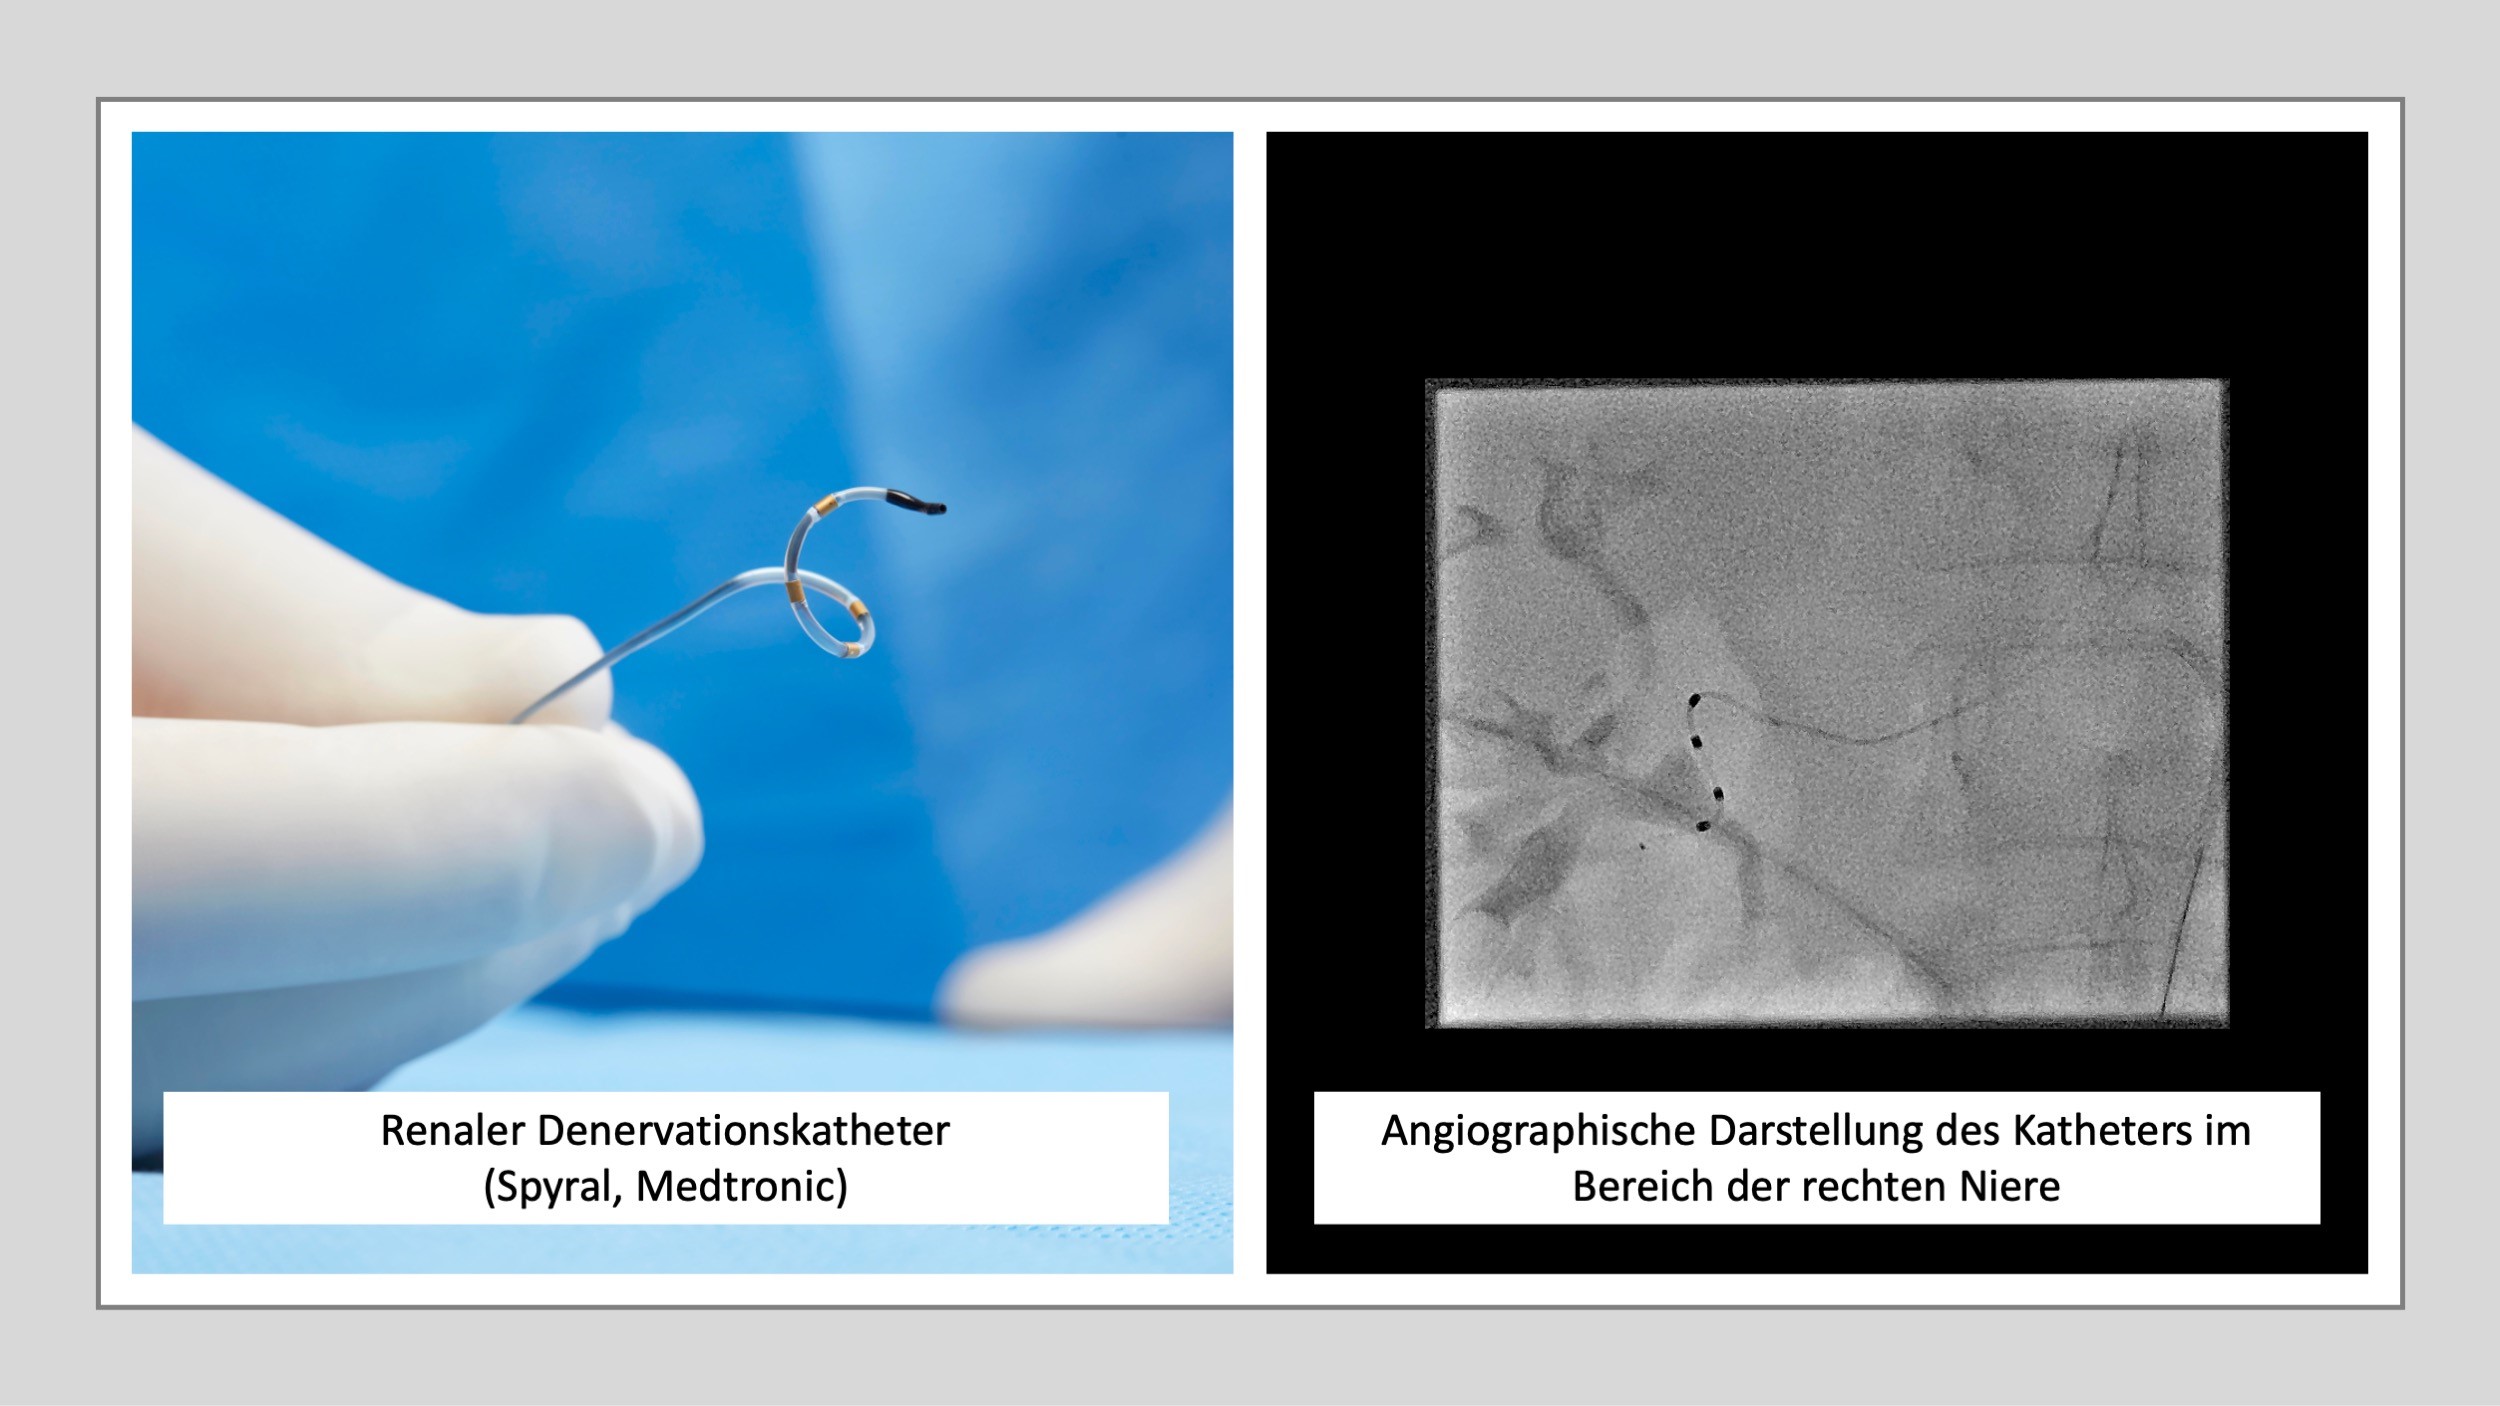

Die renale Denervation ist ein minimalinvasives Verfahren zur Behandlung der arteriellen Hypertonie (Bluthochdruck), insbesondere bei Patienten, deren Blutdruck trotz Medikamenteneinnahme nicht ausreichend kontrolliert werden kann.

Bei diesem Eingriff werden über einen Katheter, der meist über die Leistenarterie eingeführt wird, gezielt Nervenfasern in den Wänden der Nierenarterien verödet. Diese Nerven sind Teil des sympathischen Nervensystems und tragen zur Blutdruckregulation bei. Durch die Denervation wird die Aktivität dieser Nerven reduziert, was zu einer Senkung des Blutdrucks führt.

Die renale Denervation dauert in der Regel etwa 30 bis 60 Minuten und erfolgt unter lokaler Betäubung. Sie wird in spezialisierten Zentren durchgeführt und kann dazu beitragen, die Zahl der benötigten Medikamente zu reduzieren oder den Blutdruck bei therapieresistentem Bluthochdruck zu verbessern.

Denervierungskatheter und angiographische Darstellung des Katheters im Bereich der rechten Niere